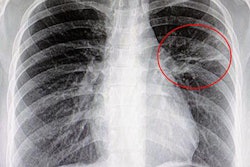

The researchers believe the findings indicate that radiography's performance varies greatly depending on whether uncertain findings are included in the mix. When they aren't -- as indicated in scenario 5 -- x-ray works about as well as indicated in the literature.

But uncertain findings do occur in the real world. And when they are included, radiography's performance dives considerably, with either sharply lower specificity, as in scenarios 1 and 2, or much lower sensitivity, as in scenarios 3 and 4.

"Pneumonia can present atypically, so including patients with only the classic symptoms of pneumonia misses a proportion of cases that are already difficult to diagnose," the authors wrote. "In this retrospective study, we found that uncertain results not only are prevalent but also affect the statistical measures of performance of chest radiography and result in wide-ranging values."

"Uncertain chest radiograph results affect the statistical measures of performance of chest radiography to a much greater degree than uncertain CT results," the authors concluded. "The poor statistical measures of performance of chest radiography for identifying pneumonia may translate into both the underdiagnosis and overdiagnosis of pneumonia."